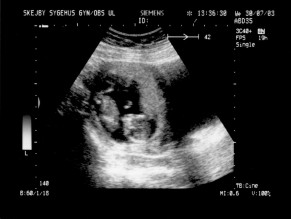

Ultralydsskanning den 30. juli 2003

Vi har i dag været på Skejby Sygehus og få foretaget en ultralydsskanning af baby. Der var kun én (pyh)! Baby blev målt og gennemset for eventuelle misdannelser. Der blev set efter at kraniet var begyndt at blive dannet og at der var to hjernehalvdele. Vi så to arme og to ben og der var fem fingre på den hånd vi så. Vi så også hjertet slå. Til sidst blev der blev målt bredden på nakkenfolden for at vurdere risikoen for mongolisme. Man kan læse mere om ultralydsskanningen her.

Konklussionen var, at alt var som det skulle være, men baby selv var ikke tilfreds. Den lå og sparkede og slog omkring sig og tog sig til hovedet.

Du kan se de billeder vi fik fra skanningen herunder.